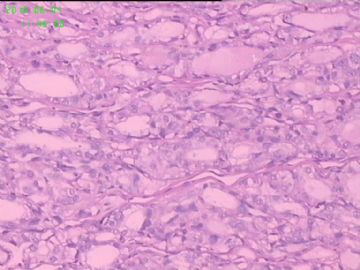

灰白结节2枚,其一2.5x1.8x1.5cm,包膜完整,内为褐色胶质,其二3x2.5x1.5cm包膜完整,切面灰白实性。附件镜下为后者。

可能楼主看到那些核的变化吧?但是没有其他支持的条件,还是应该是结甲。

就这几幅图似乎不够说明问题,细胞有一定的异型性,但是,最好能采到交界处的情况再判断。癌与非癌,最好能有组织结构与细胞异型性结合来看。

有些核透明,无其它特点,恶性证据是没有。

要看肿瘤包膜情况。